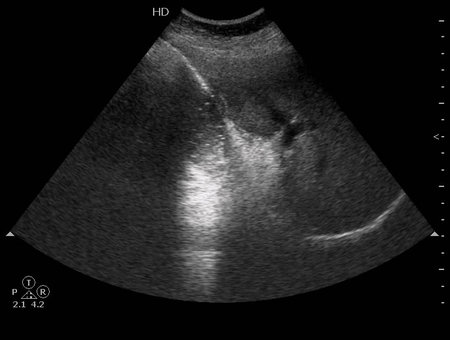

УЗИ желчного пузыря: острый эмфизематозный холецистит

Пожилая женщина с болями в правом подреберье, высокой температурой.

Деструктивный холецистит. Газ в просвете желчного пузыря.

гангренозный холецистит, перфорация передней стенки?

Все верно, острый эмфизематозный холецистит.

На операции диагноз подтвердился.